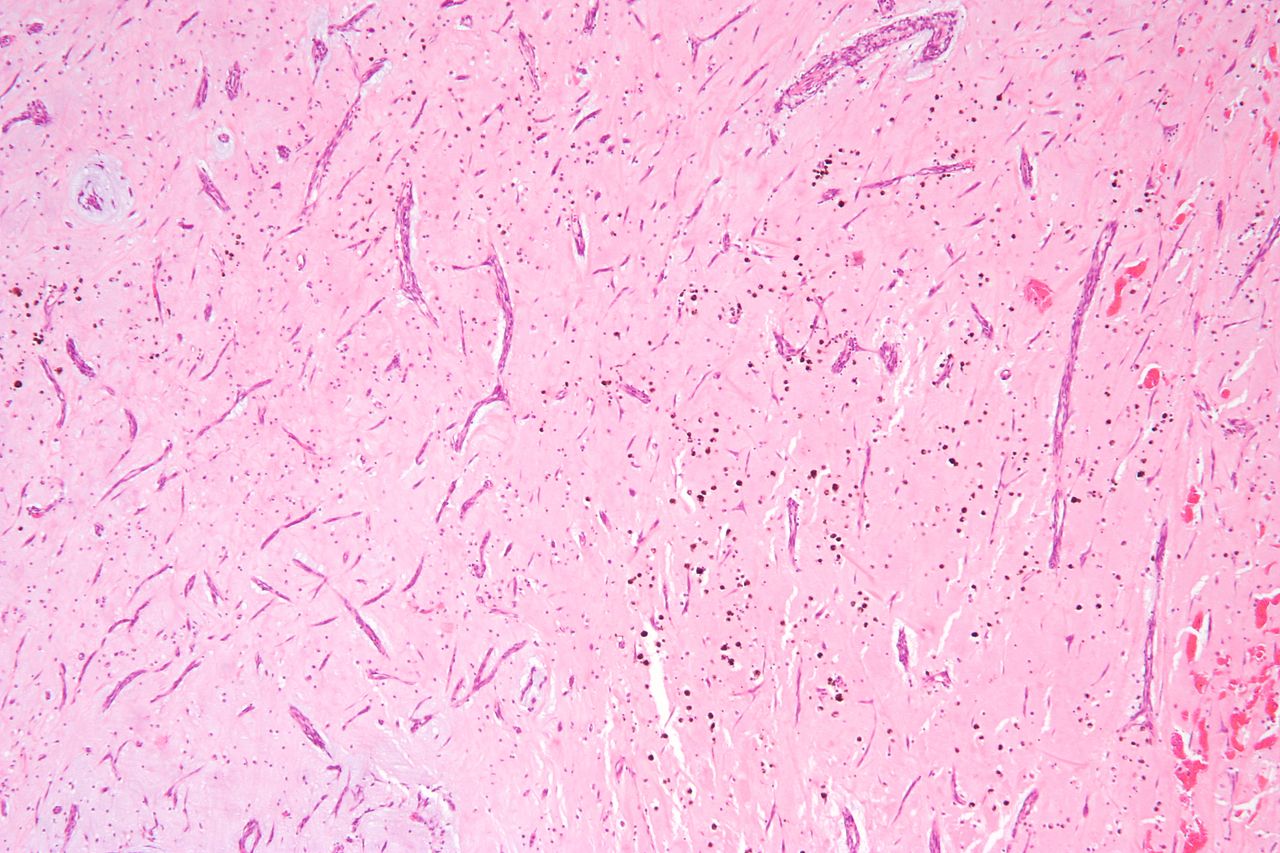

19. What histologic finding is likely in a patient with a mid-diastolic rumbling murmur best heard at the apex, positional dyspnea, a large pedunculated mass attached to the left atrium, fever, and weight loss?

Explanation

The patient's presentation is most consistent with an atrial myxoma, characterized by a large pedunculated mass attached to the left atrium. The histologic findings often include scattered cells within a mucopolysaccharide stroma and excessive vascular growth with hemorrhaging. This differentiates it from the other incorrect options provided.